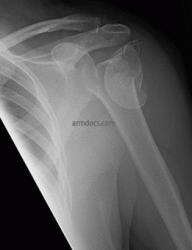

fracture of the proximal humerus in a 60 year old lady

Complex fracture of the proximal humerus in a 60 year old lady